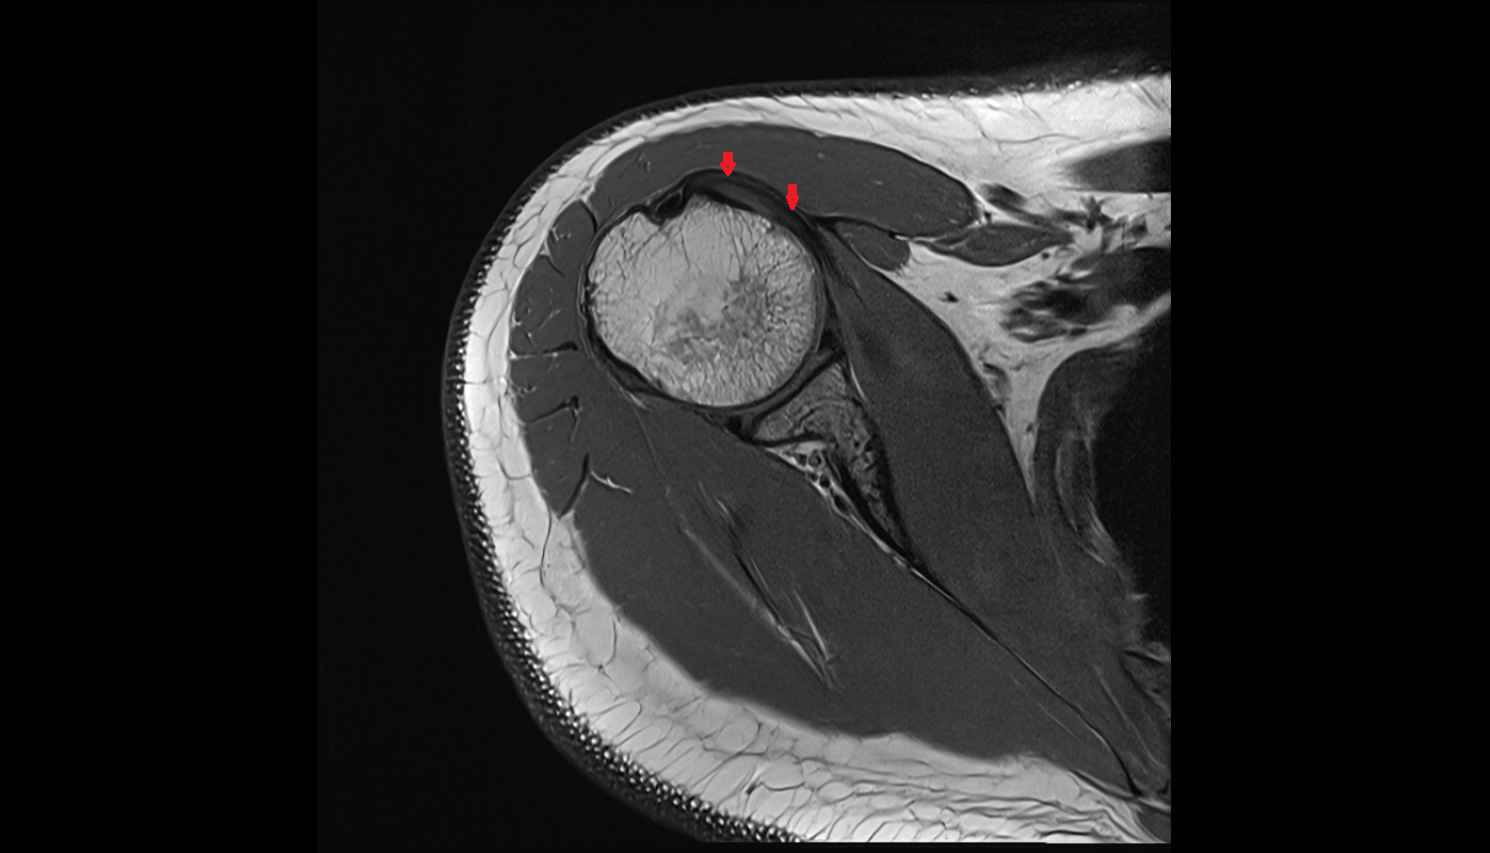

- Supraspinatus tendon